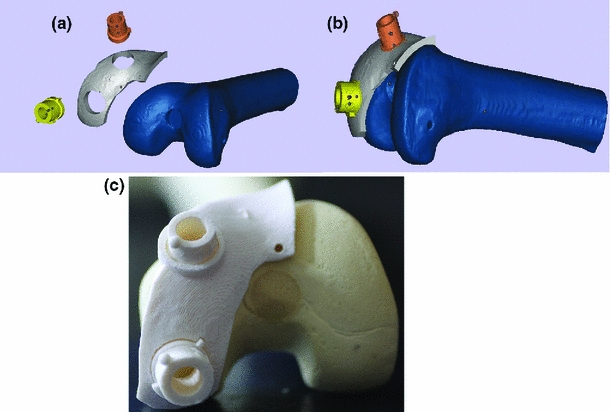

Computer intervention removes much of the human error and guesswork. My (collaborative) work has taken two forms: (1) thermoplastic custom 3D-printed templates (customized jigs), and (2) opto-electronic tracking of surgical tools.

One approach uses thermo-plastic templates. Using reconstructed patient knee models, surgical sites are planned and used to design thermoplastic templates that are 3D-printed. These templates fit the patient’s joint and guide the surgical instrument from harvest to recipient site (accounting for 6 degrees of freedom).

My work showed this method to be significantly more accurate (in customized bone models) than the conventional procedure, with reduced variance. The shortcoming is that it requires a more invasive opening of the joint cavity compared to the opto-electronic method.